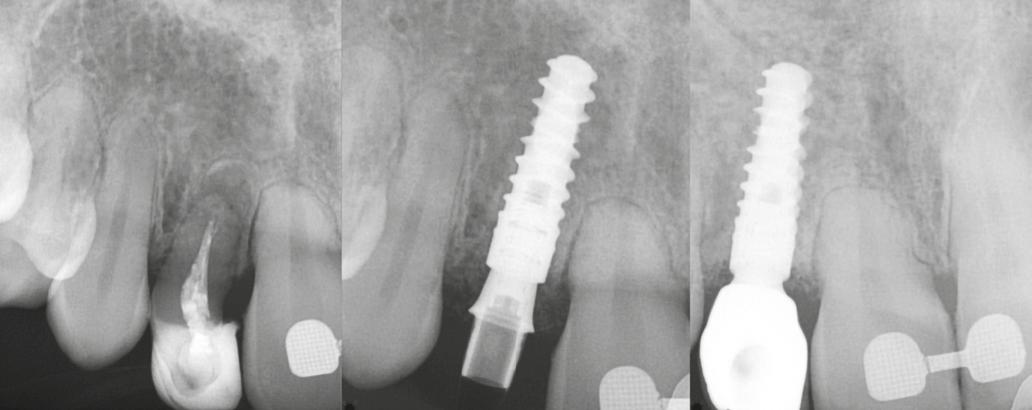

A sebészeti eljárás

Mind a hat implantátum esetén kétlépcsős műtétet végeztünk. Minden sebészeti eljárást bódítás, illetve preoperatív szisztémás antibiotikus terápia nélkül végeztünk. A négy eset közül kettőnél leukocitában és vérlemezkében gazdag fibrint (L-PRF) alkalmaztunk a beavatkozás során (IntraSpin, BioHorizons; 2. táblázat). Minden esetben a pontos CERALOG menetvágási (maximum 15 ford./perc) és fúrási (maximális fúrási fordulatszám: 550–800 ford./perc) protokollt követtük. Az összes implantátumot manuálisan helyeztük be 35 Ncm maximális nyomatékkal. Az implantátumokba PEEK zárócsavar került (2. ábra). A lágyszövetet atraumatikus, felszívódó varrattal, szorosan zártuk/összevarrtuk. A műtétek után szövődmények nem jelentkeztek. A pácienseket arra kértük, hogy a műtét utáni héten naponta kétszer öblögessenek klórhexidinnel (PERIO-AID, 0,05%, DENTAID). Az alsó állcsontnál három hónapos, a felső állcsontnál öt hónapos gyógyulási időt vettünk figyelembe. Három hónap (1. eset) és öt hónap (2., 3. és 4. eset) elteltével a műtétek második stádiumát helyi érzéstelenítés mellett végeztük. A gyógyu-

lási csavarokat (PEEK titáncsavarral) maximum 15 Ncm-rel húztuk meg (3–6. ábra). Az összes implantátum kiváló stabilitást mutatott (a mérésekhez Periotestet használtunk, a Medizintechnik Gulden jóvoltából), és teljesen osszeointegrálódott. Ezt a radiológiai vizsgálatok is megerősítették.

2. a–d ábra: PEEK zárócsavarok az implantátumokba helyezve, 1. eset (a). 2. eset (b). 3. eset (c), 4. eset (d). 3. a–b ábra: Röntgenfelvételek három hónap után (a) és a gyógyulási csavarok behelyezve (b, 1. eset). 4. a–b ábra: Röntgenfelvételek öt hónappal később (a) és a gyógyulási csavarok behelyezve (b, 2. eset). 2. táblázat: Az implantátum tulajdonságai.

Röntgenfelvételek öt hónappal később (a) és a gyógyulási csavarok behelyezve (b és c, 3. eset).

6. a–b ábra: Röntgenfelvételek öt hónappal később (a) és a gyógyulási csavarok behelyezve (b, 4. eset).